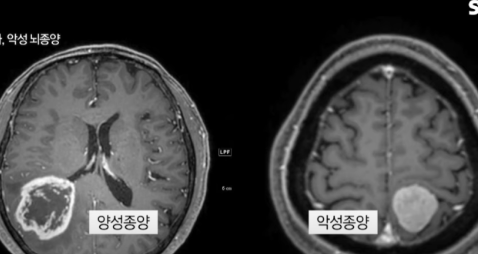

뇌암은 말 그대로 뇌 조직 안에서 비정상 세포가 증식해 종양을 만드는 질환입니다. 크게 두 종류로 나뉩니다.

- 원발성 뇌종양: 뇌나 뇌를 싸는 조직에서 직접 발생한 종양(예: 교모세포종(glioblastoma), 성상세포종(glioma), 수막종(meningioma) 등).

- 영상검사: MRI(조영증강) — 가장 민감하고 표준적인 검사. 필요시 CT, MR spectroscopy, PET 등 보조 검사를 사용.